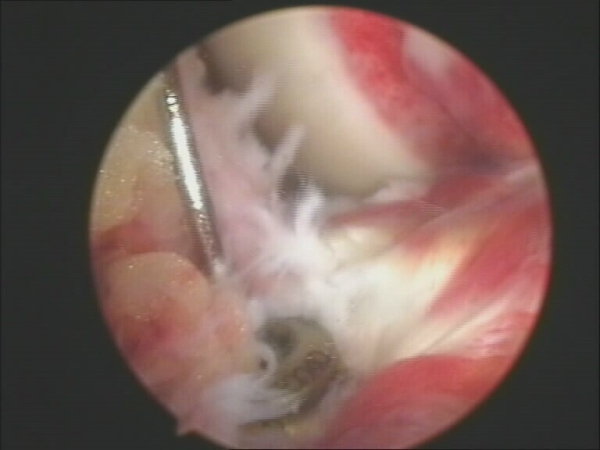

采取硬腰联合麻醉,患肢上气囊止血带;关节镜常规入路,探查膝关节;观察前交叉韧带胫骨止点撕脱骨折块大小、粉碎情况及移位程度;探查是否合并半月板、交叉韧带及软骨面的损伤;清除骨折块与胫骨之间游离滑膜组织;陈旧性骨折设法与骨折块分离,修整为新鲜创面;用探针将骨块连同韧带拉向胫骨骨床。评估前交叉韧带紧张程度,若发现骨块与骨床不匹配,可将骨床挖深3-5mm,将骨块复位。膝关节屈曲位,紧贴髌骨内侧缘切开皮肤0.5cm,将1.5mm克氏针从髌内侧缘穿入骨折块暂时固定,进针点尽量靠近前交叉韧带基底部,关节伸直位观察骨折块复位及稳定情况,放入带齿垫片,拧入空心螺钉将带齿垫片牢固固定于前交叉韧带的基底部(如图2),之后拔除克氏针。关节镜监视下,活动膝关节,对存在髁间撞击患者,行髁间窝成形术。固定完成后,关节镜下探查前交叉韧带走行及张力,并行前抽屉试验检查膝关节稳定程度。合并损伤进行相应处理,对损伤半月板尽量修复或行部分切除;对增生、充血滑膜行清除;髌股关节及胫股关节软骨损伤进行病灶清理;骨赘形成进行清理。

图2 关节镜下使用空心螺钉及带齿垫片固定前交叉胫骨止点撕脱骨折